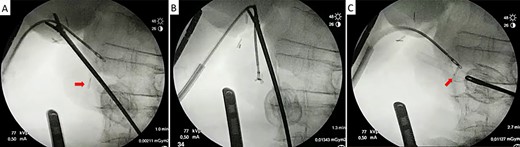

Laparoscopic transcystic extraction under intraoperative radiological guidance. Without any contrast injection to facilitate titanium visualization, the metallic clip (red arrow) is recognized in the distal CBD (A), caught with the endoscopic forceps (B) and finally removed from the CBD through the cystic duct (C).